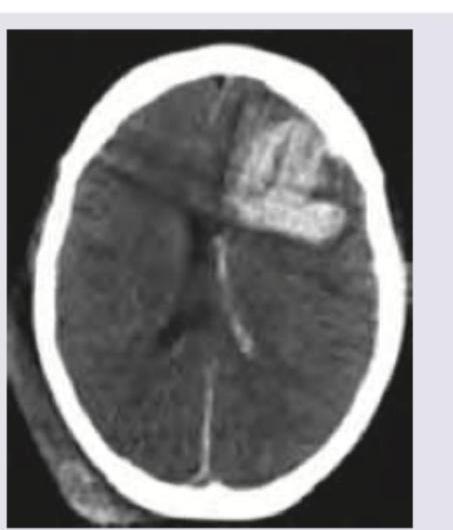

Which of the following is correct about the NCCT shown below? (Recent NEET Pattern 2016-17)

Explanation: ***Left intraparenchymal hemorrhage*** - This **NCCT image** demonstrates a **hyperdense lesion** (bright white area) within the **frontal lobe** of the brain. - The location is clearly within the **brain parenchyma** and on the **left side** of the image, indicating an intraparenchymal hemorrhage. *Left intraventricular hemorrhage* - This would appear as hyperdensity **within the ventricles**, which are the fluid-filled spaces of the brain. - The hemorrhage in the image is located in the brain tissue, not within a ventricular cavity. *Right intraventricular hemorrhage* - A right intraventricular hemorrhage would be seen as hyperdensity **within the right ventricle**. - The lesion shown is on the opposite side (left) and within the brain parenchyma, not in the ventricular system. *Right intraparenchymal hemorrhage* - This would appear as a hyperdense lesion **within the brain parenchyma on the right side of the brain**. - The hemorrhage visible in the image is clearly situated on the **left side**, ruling out a right-sided hemorrhage.

Explanation: ***Intraparenchymal hemorrhage*** - The image shows a **hyperdense (bright)** lesion within the brain parenchyma, indicated by the arrows. This appearance on non-contrast CT (NCCT) is characteristic of **acute hemorrhage** (blood) within the brain tissue. - The location and morphology are consistent with blood accumulating directly within the brain substance rather than in the subarachnoid space or as a diffuse cerebral edema. *Acute ischemic stroke* - An **acute ischemic stroke** on NCCT typically appears as a **hypodense (darker)** area due to **edema** and cell death, usually after several hours. The lesion shown in the image is hyperdense. - Early signs of acute ischemic stroke (within the first few hours) can include subtle changes like loss of gray-white matter differentiation or hyperdense vessel signs, but not a distinct hyperdense parenchymal lesion as seen here. *Acute hemorrhagic stroke* - While technically a hemorrhagic stroke, this option is too broad. Hemorrhagic stroke encompasses both intraparenchymal hemorrhage and subarachnoid hemorrhage. - The specific location of the blood within the brain tissue, as opposed to solely in the subarachnoid space, makes "intraparenchymal hemorrhage" a more precise diagnosis. *Subarachnoid hemorrhage* - **Subarachnoid hemorrhage (SAH)** would appear as hyperdensity (blood) in the **sulci, fissures**, and **basal cisterns** surrounding the brain, not within the brain parenchyma itself. - The image clearly shows the lesion within the brain tissue, not in the subarachnoid spaces.